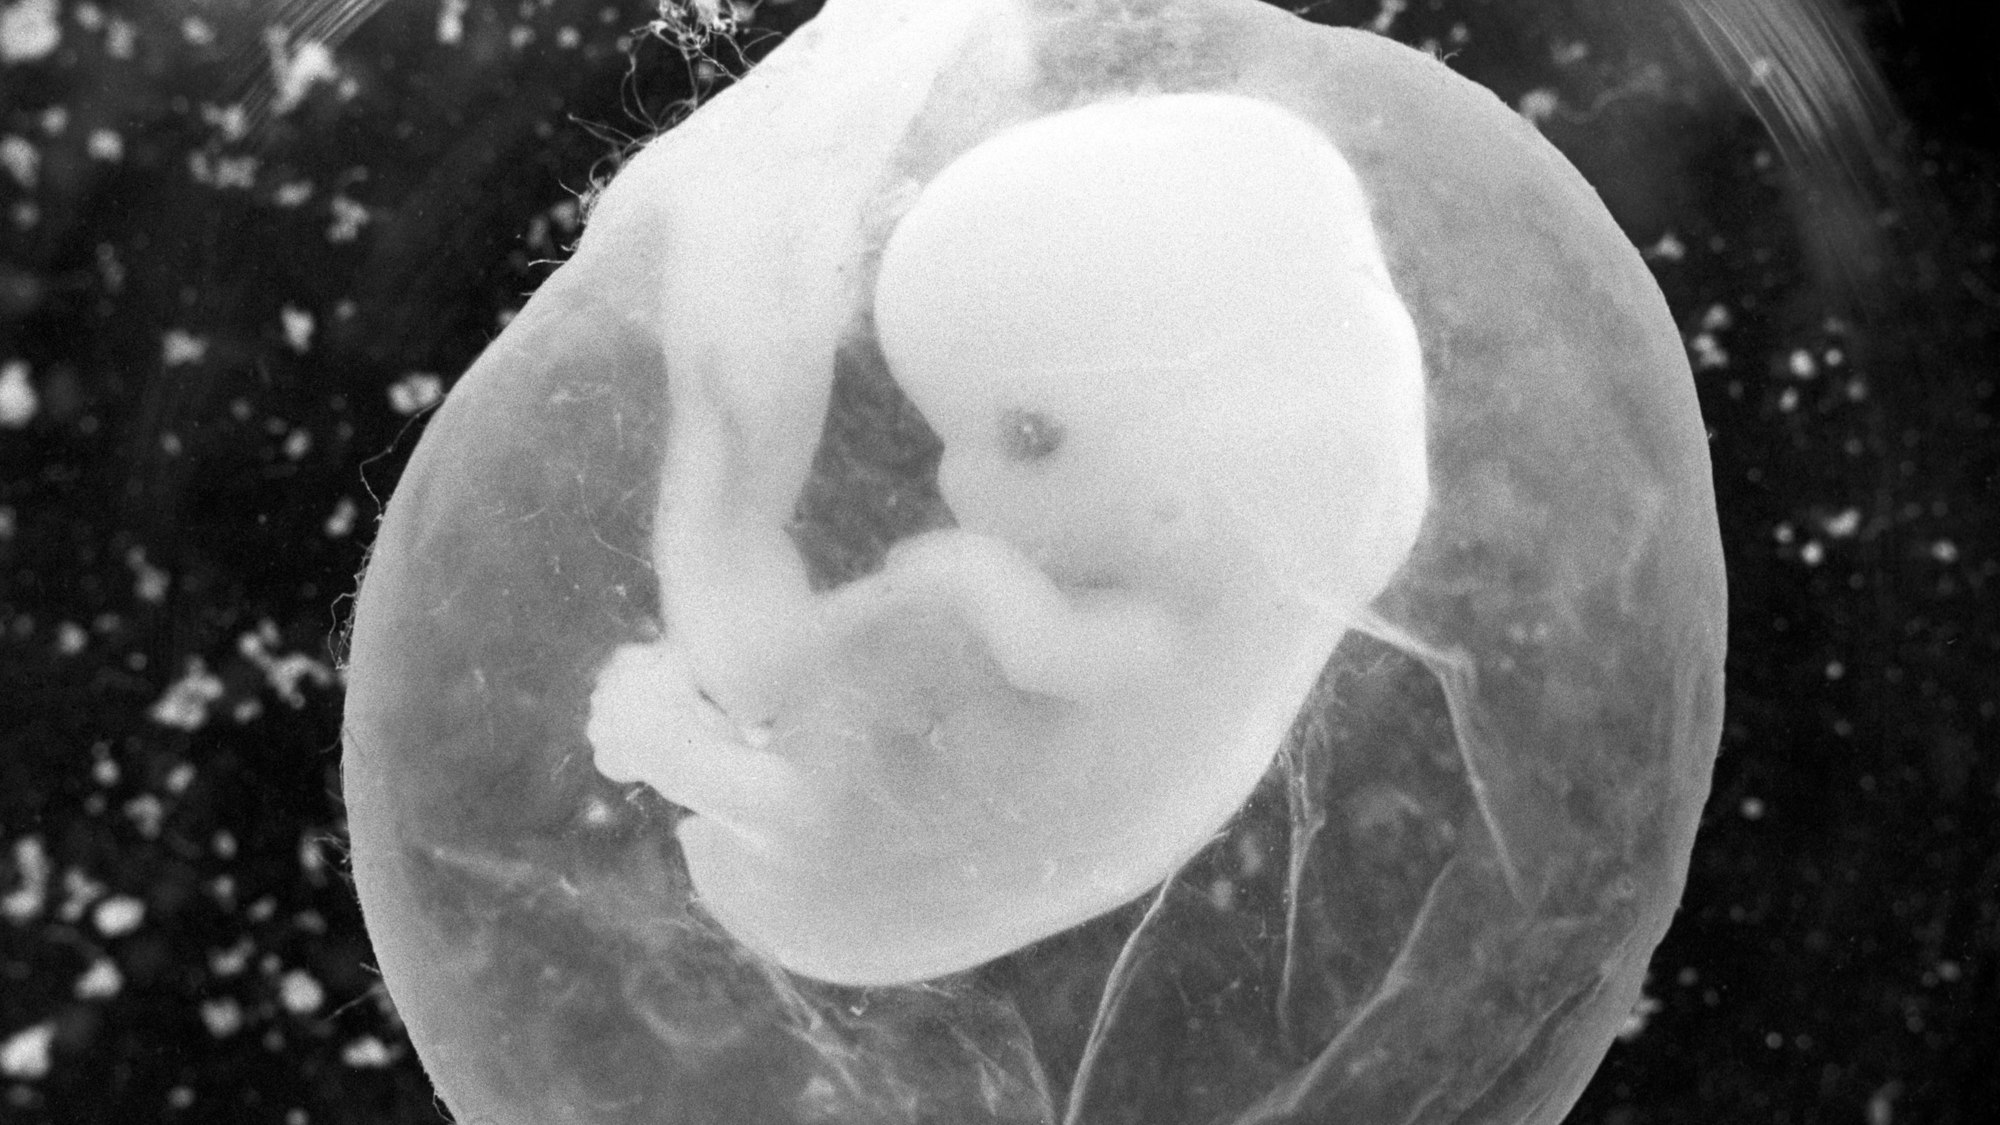

Sieben Wochen alt ist dieser Embryo in seiner Fruchtblase, von der achten Woche an sprechen Mediziner von einem Fötus.

Copyright: picture alliance / dpa